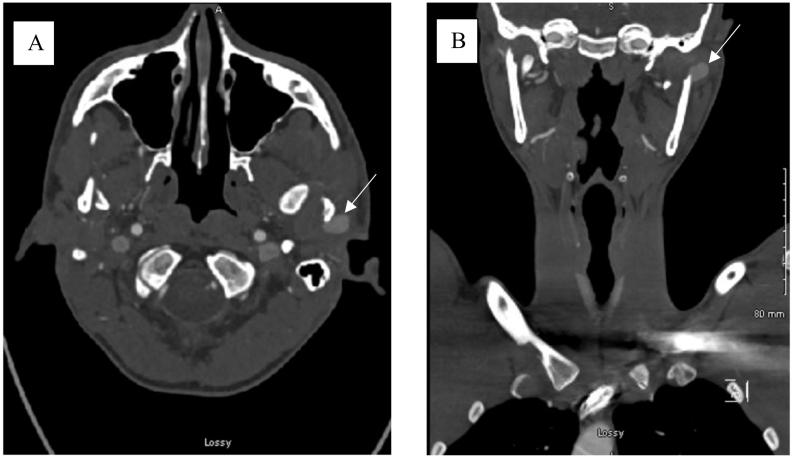

A traumatic pseudoaneurysm of the superficial temporal artery is a rare vascular lesion that typically occurs after blunt trauma to the temporal region. It accounts for only 1% of all traumatic aneurysms. These pseudoaneurysms need to be appropriately diagnosed and treated without delay as the patient can experience resulting symptoms of severe headache, facial nerve palsy, arterial bleeding, and/or bone erosion. Diagnosis can typically be made with history of trauma along with physical examination followed by confirmation with ultrasound or computer tomography angiogram. The treatment of choice is ligation and resection. We present a case of a 20-year-old male with identified pseudoaneurysm following facial trauma and mandibular fracture repair treated with multiple trials of sclerotherapy. In addition, this report will review additional management options and diagnosis techniques for superficial temporal artery (STA) pseudoaneurysms.